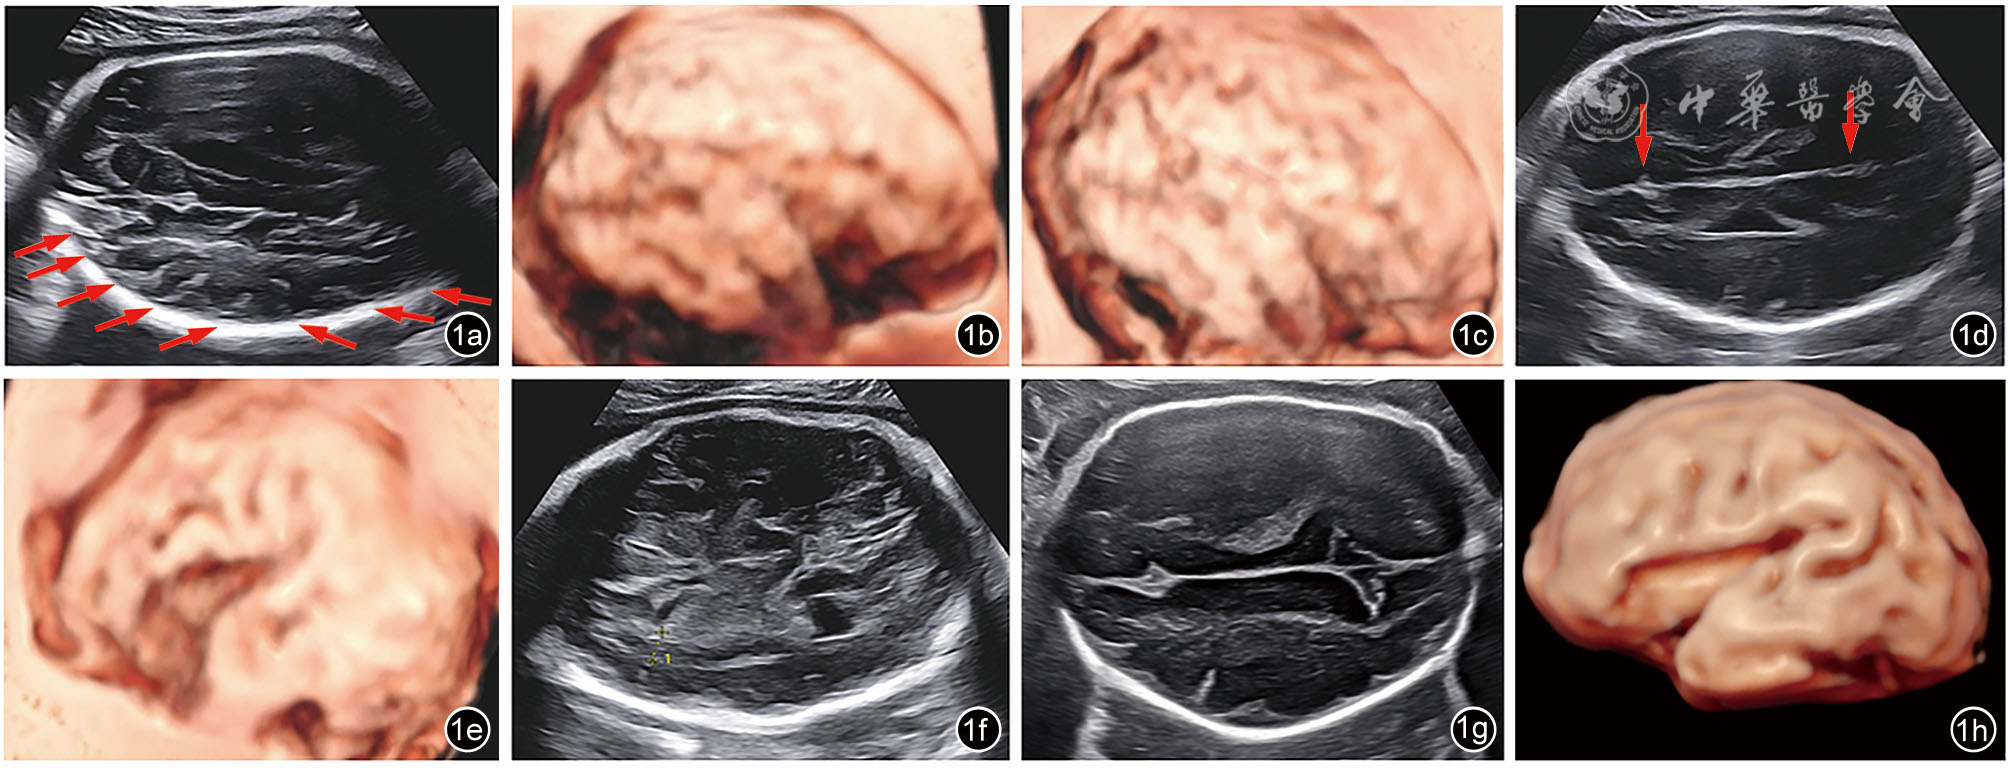

图1 孕29+6周胎儿巨脑畸形-多小脑回综合征的超声表现。图a示额叶、枕叶可见异常细浅沟回,呈锯齿样改变(箭头所示);图b、c示三维反转成像可见多小脑回;图d箭头分别示扣带沟及顶枕沟浅;图e三维反转成像可见外侧裂浅;图f量标示脑实质分层明显;图g示正常同孕龄胎儿扣带沟、顶枕沟;图h示正常同孕龄大脑三维反转成像

孕妇35岁,孕3产1,夫妻均体健,非近亲结婚,否认孕前、孕期毒物与放射线接触史,否认家族遗传病史。2023年3月开始于深圳市妇幼保健院规律产检。自然受孕,经早孕期孕8周超声核对末次月经及预产期无误。停经12周胎儿超声提示:胎儿大小相当于13+4周,颈项透明层厚度(nuchal translucency,NT)1.7 mm,胎儿鼻骨可见,心脏声像改变提示右位主动脉弓。经遗传学咨询后,于16+2周行羊膜腔穿刺,采集胎儿羊水进行染色体核型分析+染色体微阵列分析,结果均未见异常。孕22+1周行Ⅲ级超声检查:胎儿大小相当于25+1周。胎儿右位主动脉弓,左锁骨下动脉迷走,左位动脉导管,其与左锁骨下动脉相连,动脉导管、左锁骨下动脉及主动脉弓三者形成“U”形血管环,局部气管受压,受压段宽约0.17 cm,其上段宽约0.27 cm。胎儿头围位于均数+3.49标准差,腹围位于均数+3.02标准差,体重位于第99.95百分位[参考美国国家儿童健康与人类发展研究所(National Institute of Child Health and Human Development,NICHD)曲线],胎儿左侧侧脑室宽约0.96 cm。胎儿永久性右脐静脉。由于胎儿超声出现新表型“大头畸形”及“过度生长”,原有羊水DNA进一步检测甲基化特异性多重连接探针项目排查Beckwith-Wiedemann综合征,结果为阴性;孕妇拒绝同时行家系全外显子组测序(whole exome sequencing,WES)。孕26周孕妇诊断为“妊娠期糖尿病”。孕26+1周复查超声提示胎儿头围进行性增大:胎儿头围位于均数+4.96标准差,腹围位于均数+2.88标准差,体重位于第99.95百分位,胎儿左侧侧脑室宽约0.92 cm。再次告知原有羊水检测项目的局限性,夫妻知情同意原有羊水DNA进一步行WES,结果提示,在PIK3CA基因上检出与胎儿临床表型相符的可能致病变异:NM_006218.4:c.1346C>T(p.Pro449Leu)杂合变异,经夫妻双方外周血验证均为野生型,为新发变异。孕妇于孕29+6周再次复查超声提示:胎儿大小相当于35+2周,胎儿头围位于均数+6.2标准差,胎儿颅脑声像改变:巨头畸形、多小脑回(图1a~1c)、外侧裂及顶枕沟浅(图1d、1e),脑实质分层明显(图1f)、左侧脑室宽1.3 cm。胎儿右位主动脉弓,左锁骨下动脉迷走并“U”形血管环形成。胎儿永久右脐静脉。孕30周行胎儿头颅MRI检查提示(图2):胎儿巨头,多小脑回畸形,双侧脑室增宽,胎儿额枕径位于均值+4标准差以上水平,双顶径、骨双顶径、胼胝体长度位于均值+3标准差以上水平,小脑蚓部前后径位于均值+2标准差以上水平,小脑蚓部高度位于均值+7标准差以上水平。根据多次超声及MRI结果,胎儿可诊断为脑皮质发育畸形(malformations of cortical development,MCD),综合基因检测结果及产前影像学表现,提示胎儿预后不良,孕妇及家属知情并于孕31+3周引产,胎儿出生体重2940 g,头围34 cm,胸围33 cm,腹围33 cm,身长49 cm,外观未见明显异常,未行胎儿尸解。本病例报道通过深圳市妇幼保健院伦理委员会批准(批件号:KYYS-2025-039)。